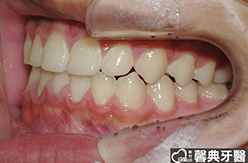

上、下顎前突,俗稱暴牙,由於上下前牙向前暴出,在外觀上容易產生牙齒外露的現象,雙唇較難自然閉合,嘴唇看也來也會比較厚。

患者︰趙同學,20多歲,學生。

主訴︰齒列不正,暴牙,不好看。

治療計劃︰上下顎齒列平整、後縮,重建正常咬合關係。

| ●治療前 | ●治療後 | |